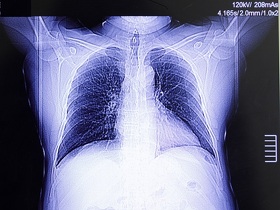

Кардіобригада невідкладної допомоги прибуває на місце виклику на спеціалізованому автомобілі, який має назву кардіомобіль, з відповідним медичним оснащенням. У розпорядженні лікарів є прилади для обстеження пацієнта, стан якого характеризується як невідкладний, та засоби для надання екстреної допомоги. Це електрокардіограф, кардіомонітор, тонометр, фонендоскоп, пульсоксиметр, дефібрилятор, апарат штучної вентиляції легень, вимірювання рівня цукру у крові, перев'язувальний матеріал, лікарські препарати.

При наданні екстреної медичної допомоги при серцево-судинних захворюваннях лікарі кардіобригади проводять ЕКГ, контролюють частоту серцевих скорочень, артеріальний тиск, виконують швидкий тест на тропонін, перевіряють рівень цукру у крові, насиченість крові киснем (сатурацію) та низку інших життєвих показників пацієнта.